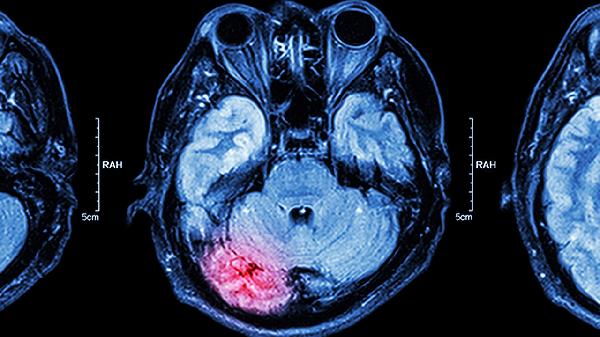

慢性脑供血不足可通过调整生活方式、控制基础疾病、药物治疗、物理治疗、手术治疗等方式改善。慢性脑供血不足通常由动脉粥样硬化、高血压、颈椎病、心脏疾病、血液黏稠度增高等原因引起。